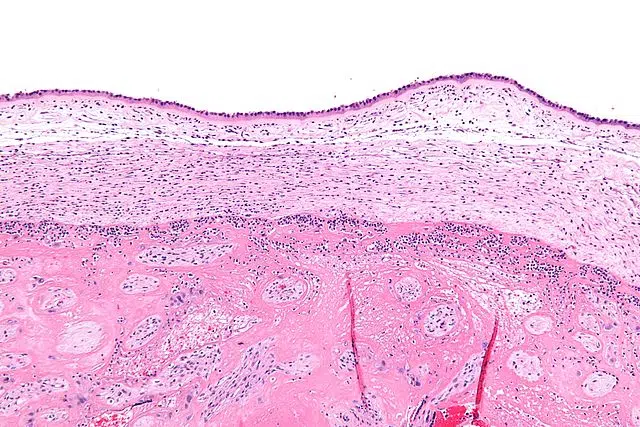

Os critérios de Gibbs são uma série de diretrizes clínicas classicamente utilizadas para o diagnóstico de corioamnionite. A corioamnionite é um processo inflamatório infeccioso agudo das membranas placentárias, acompanhado por uma infecção do conteúdo amniótico, isto é, do líquido amniótico, do cordão umbilical e / ou do feto.

A corioamnionite também é chamada de infecção intra-amniótica ou amnionite e pode ser acompanhada por ruptura prematura das membranas ou saco amniótico e entrega prematura. Afeta entre 2 e 11% das gestantes e, nesses casos, 5% dos fetos.